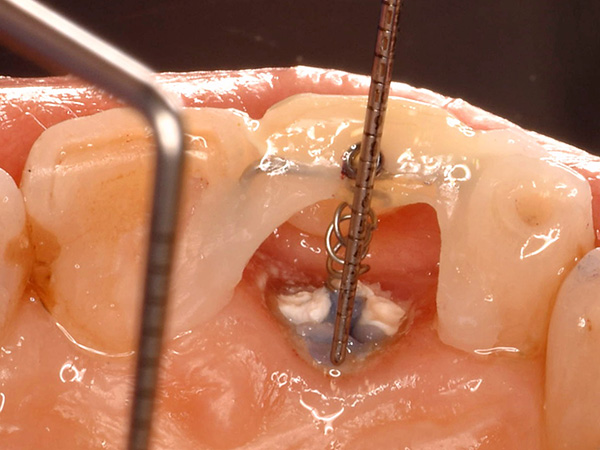

根の奥深くにひび割れが入っていたケース、その位置と深さによって、また周囲の歯質の厚みによっても矯正治療による移動距離や回転角度が異なって参ります。

『ほんとだ!回ってる、回ってる!!